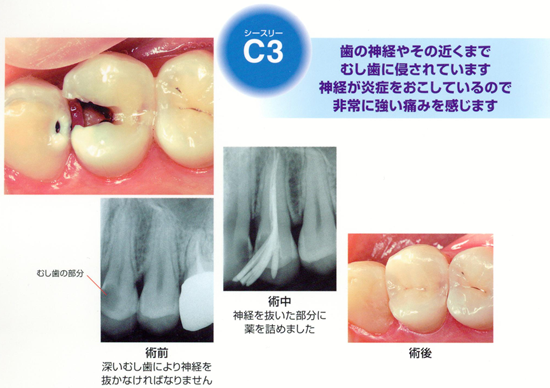

C3(シースリー)

歯の神経やその近くまで虫歯に侵されています。

神経が炎症を起こしているので、非常に強い痛みを感じます。